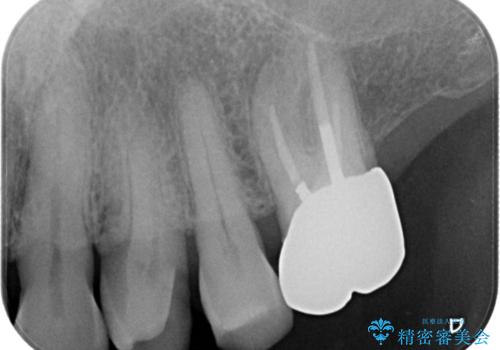

- 「フロスをしたら銀歯が取れた」を主訴に来院された患者様です。虫歯を除去した後、ゴールドインレーで治療を行いました。

左上4はゴールドインレー、左上5はCR(保険適応)で治療を行いました。